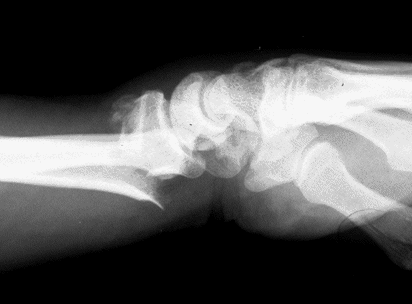

Case 1 Injury